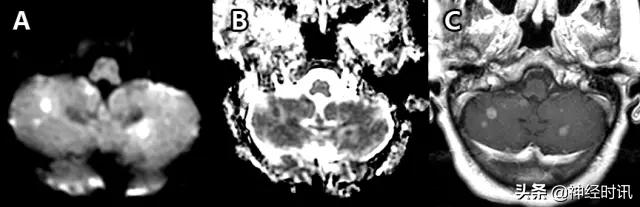

转移性病变

大量细胞转移灶,尤其是小细胞肺癌,可以表现为因致密细胞聚集所致的弥散受限,且可能与急性或亚急性栓塞性卒中相混淆(图24)。前者的一些鉴别特征包括存在周边血管性水肿、周边强化和其它的脑实质外病变(如颅骨病变)。

图24 一位51岁的女性小细胞肺癌患者,因每天早晨突然出现的恶心、呕吐而就诊。其小脑存在多发性弥散受限病灶(A:DWI,B:ADC),并伴有强化(C:T1WI增强扫描)。